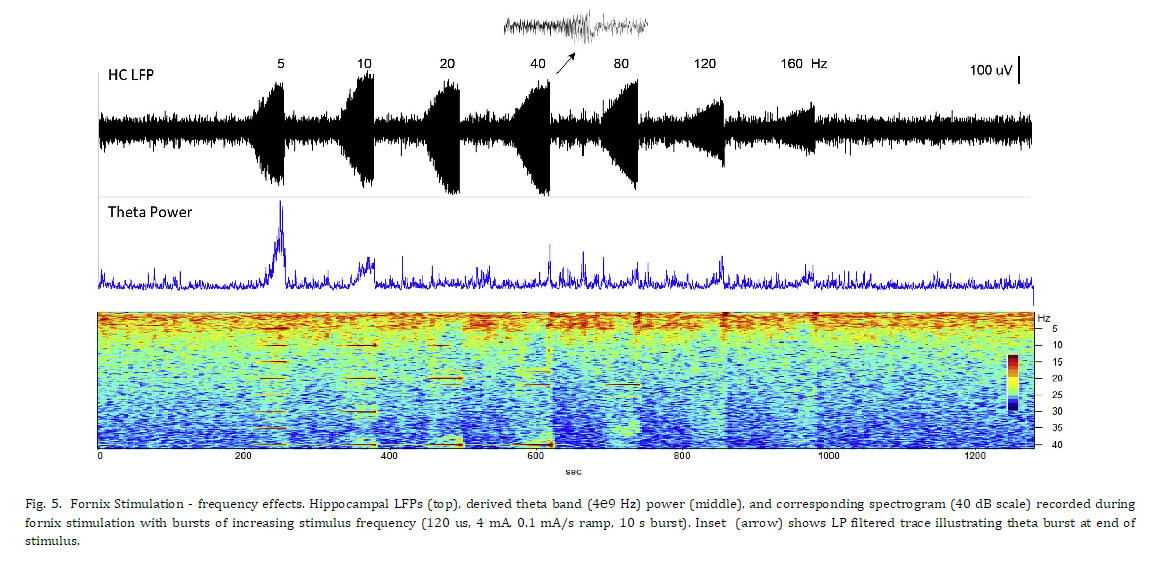

시상 자극에 대한 초기 연구와 직접적인 비교를 제공하기 위해 해마 LFP 활동에 대한 다양한 자극 진폭 및 빈도의 효과를 평가했습니다. 그림 4는 증가하는 진폭의 자극(40Hz)의 10초 램프 시작 버스트에 대한 해마에 기록된 반응을 보여줍니다. 더 낮은 자극 진폭에서 해마 활동의 억제가 있었고 자극 중에 발생한 세타 및 더 높은 주파수 대역에서 분명했지만 이월 효과는 거의 없었습니다. 자극 진폭이 증가함에 따라 이 억제 효과는 그림 4에 제시된 마지막 두 자극에서 볼 수 있는 세타 활동의 임계치 의존적 흥분 폭발로 전환되었습니다. 더 높은 주파수 대역(베타, 감마)이 감소된 낮은 주파수 성분(델타, 세타). 서로 다른 주파수의 Fornix DBS(그림 5)는 유사한 응답 패턴을 생성했으며 자극 진폭의 느린 증가 동안 20Hz 이상의 자극 주파수에서 LFP 억제가 분명했습니다. 이 예에서, 자극 수준이 프로그래밍된 최대값(4mA)에 도달함에 따라 더 높은 DBS 주파수로 생성된 세타 활동의 짧은 버스트(삽입)가 있었고, 이어서 낮은 주파수 LFP 활동이 상승했습니다. 이러한 자극으로 인한 세타 버스트는 오래 지속되는 효과를 가졌습니다. 그림 6에 보다 명확하게 설명된 것처럼 기본 해마 LFP 활동에 대해 설명합니다. 이 예에서 해마 활동의 12분 기간은 피험자가 조용히 쉬고 있는 상태에서 기록되었습니다. 5분의 기준선 기간 후, 해마 세타 버스트를 생성하기 위해 문턱 이상의 수준까지 뇌궁 자극이 천천히 증가했습니다. 자극 진폭이 증가함에 따라 짧은 억제 기간이 관찰된 후 상단 패널 스펙트로그램에서 볼 수 있는 짧은 세타 버스트가 관찰되었습니다. 이 세타 버스트와 자극 중단 후 해마의 LFP 활동은 기준선과 비교하여 현저하게 변화했으며 이러한 패턴은 자극 후 몇 분 동안 지속되었습니다. 전체 시험 기간 동안 관찰된 행동 변화는 없었습니다. 이 그림의 중간 패널은 기준 기간과 자극 후 기간에 대한 평균 파워 스펙트럼의 비교를 보여줍니다. 기준선 동안 우세한 LFP 전력은 델타 대역에 있었습니다. 더 높은 주파수 베타 및 낮은 감마 활동의 버스트가 이 기간 내내 존재했으며, 이는 스펙트로그램에서 더 쉽게 볼 수 있습니다. 자극 유도 세타 버스트에 이어 델타 활동이 증가하고 세타 활동의 강한 밴드가 나타나며 더 높은 주파수에서 동시에 감소합니다. 하단 패널은 이러한 사전 및 사후에 대한 해당 위상-진폭 결합(PAC) 관계를 보여줍니다. 자극 기간. 기준선 동안 세타와 감마 활동, 세타와 높은 베타 밴드, 델타와 낮은 베타 밴드 사이에 강한 PAC가 있습니다. 자극 후 상태에서 증가된 델타 및 세타 전력에도 불구하고 이 네트워크 상태에서 관찰된 고주파 활동의 현저한 감소로 인해 이 PAC의 거의 모든 것이 감소되거나 폐지되었습니다.